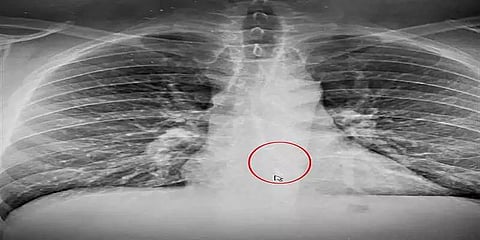

அமெரிக்காவில் 38 வயதான Brad Gauthier நெஞ்சு வலியினால் அங்குள்ள மருத்துவமனைக்கு சென்று மருத்துவரை சந்தித்துள்ளார். அவரை பரிசோதித்த மருத்துவர் ‘எதற்கும் ஒரு எக்ஸ்ரே எடுத்து பார்த்துடுவோம்’ என சொல்லி எக்ஸ்ரே எடுக்க சொல்லியுள்ளார். அதன்படியே எக்ஸ்ரேவும் எடுத்துள்ளார் அந்த நபர். அதன் ரிப்போர்ட் தான் அவருக்கு அதிர்ச்சி கொடுத்துள்ளது.

அதில் ஹெட்செட் வடிவில் ஒரு ஏர் பாட் இருந்துள்ளதை மருத்துவர் கண்டு சொல்லியுள்ளார். அதன் பிறகு தான் அந்த நபர் உட்பட அனைவருக்கும் அவர் தூங்கும் போது ஆப்பிள் ஏர் பாடை விழுங்கியுள்ளார் என்பது தெரிந்தது. அது அவரது உணவு குழாய்க்கு அருகில் சிக்கி இருந்துள்ளது.

எண்டோஸ்கோபிக் முறையின் கீழ் அதை மருத்துவர்கள் அகற்றியுள்ளனர்.